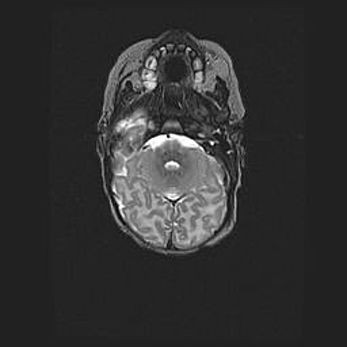

Церебральная ишемия II.

Возраст: 5 дней

Вес: 3400 г

Пол: женский

Окружность головы: 35 см

Срок гестации: 39 недель

Церебральная ишемия – это заболевание, характеризующееся недостаточностью (гипоксией) либо полным прекращением (аноксией) снабжения мозга кислородом по причине закупорки одного или нескольких сосудов. Это приводит к  что метаболическим расстройствам различной степени тяжести в тканях головного мозга, развитию коагуляционных некрозов и гибели нейронов.